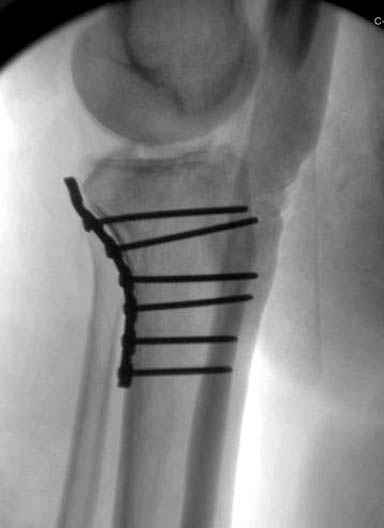

Трудно поверить, что разрекламированная Ортопедическая школа Восточной Украины позволяет такие странные снимки? На прямом снимке сохранен общий контур плато, но не известна судьба импрессии суставной поверхности. На полубоковой?, оставлен без репозиции задне-медиальный отдел, и навряд ли после такой фиксации можно удовлетвориться результатом.

Такая ситуация характерна для многих, когда принимается ошибочное решение, т.е пытаются фиксировать одним имплантом переломы двух мыщелков. Латеральная пластина приемлема только для тех случаев, когда сохраняется интактным медиальный диафизарный кортекс и отсутствует фрагментация на верхушке медиального перелома.

При сложных переломах тибиал плато для своего рода Damage Control мы иногда применяем поэтапную тактику. Сперва оперируется одна сторона, а потом после рекондиции мягких тканей окончательный этап.

Если состояние мягких тканей позволяет, я бы предложил такой метод для вашего больного. Без предварительного планирования будет трудно, но шанс не надо упускать. Всего несколько дней после операции, и такая тактика лучше, чем недовольный молодой пациент.

Доступ к медиальной стороне задний или медиальный, через pes или в пространстве между medial gastroc мышцы.